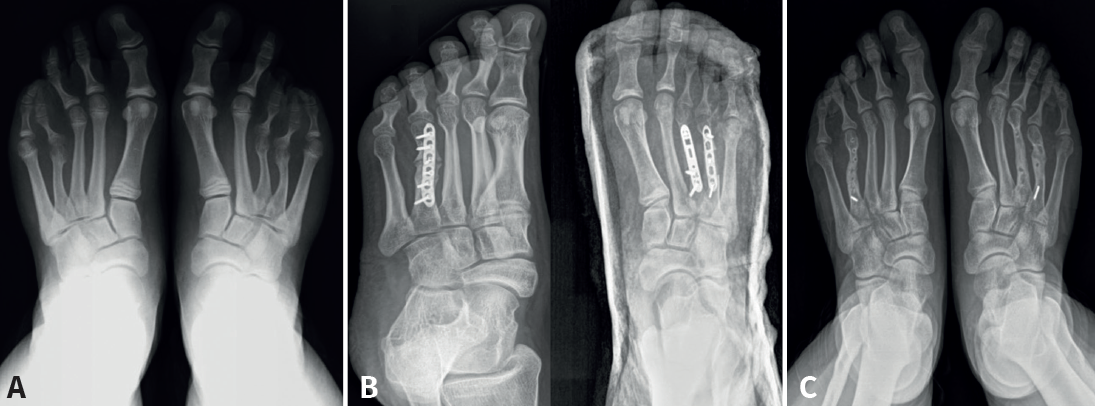

En el grupo B se optó por un alargamiento en un solo tiempo con injerto autólogo de peroné y fijación con placa según la técnica de Waizy(4). Se trataba de aquellos pacientes en los que hubiese que ganar menos de 15 mm o no toleraran el tratamiento con fijador externo. Para ello, se realizó una incisión dorsal sobre el metatarsiano afecto. Los pasos quirúrgicos fueron: alargamiento del tendón extensor largo, sección del tendón extensor corto, capsulotomía dorsal y osteotomía con sierra. Mediante una incisión de 3 cm por encima de la sindesmosis tibioperonea distal se obtuvo un cilindro de la mitad anterior del peroné como injerto autógeno con una longitud adecuada en función del acortamiento que se fuera a corregir, sin producir una pérdida de continuidad de este, puesto que se respetaba la cortical posterior. El injerto se interpuso en el plano de la osteotomía y se fijó a este con una placa Compact® de ángulo variable de 2,0 mm del sistema LCP Forefoot/Midfoot de Synthes. La primera articulación metatarsofalángica también se fijó temporalmente con una aguja de Kirschner que se mantuvo hasta 6 semanas (Figura 2). Tras la cirugía se indicaron 6 semanas de yeso en descarga y posteriormente 6 semanas más de carga protegida con ortesis Cam-Walker.